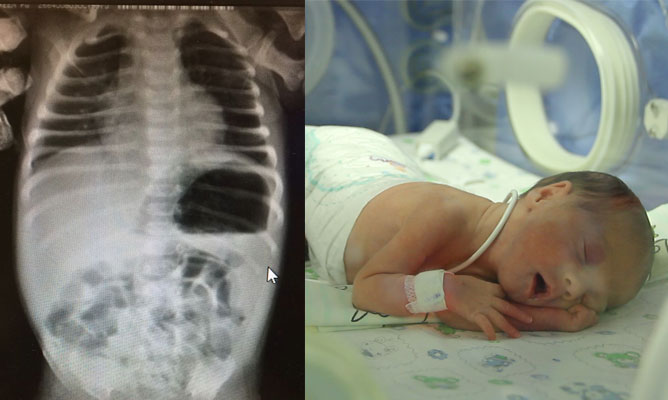

Mərkəzi Klinikada nadir rast gəlinən, bağırsaqların anadangəlmə inkişaf qüsuru ilə körpə doğuldu.

Bətndaxili Ultrasəs müayinəsində bağırsaqlarında ciddi genişlənmə görülən körpə 37 həftəliyində, 3200qr doğuldu.

Doğulduqdan dərhal sonra qarnında ciddi köp, ödlü qusmaları olduğu üçün aparılan müayinələr nəticəsində nazik bağırsağın anadangəlmə qapalı olduğu düşünülərək təcili cərrahi əməliyyata alındı. Əməliyyat zamanı Tibbi ədəbiyyatda soyulmuş alma qabığına bənzədilən nadir və olduqca ağır patologiya İleal atreziya (tip lll B Apple peel,Christmas tree) yəni nazik bağırsağın uc hissəsinin bağlı olduğu, yoğun bağırsağın da bətndaxili (unused kolon) işləmədiyi görüldü.

Nazik bağırsağın qapalı hissəsi kəsilib çıxarıldı, İleoçekal anastamoz yəni nazik bağırsağa yoğun bağırsağa tikildi.

Yanaşı ürək qüsurları olan körpə əməliyyatdan sonra yenidoğulmuşların reanimasiya şöbəsinə yatızdırıldı. Pediatriya şöbəsinin həkim kollektivinin gərgin səyləri nəticəsində körpə tam sağlam şəkildə evə yola salındı.